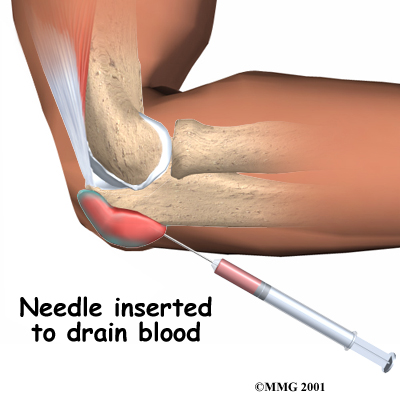

If your doctor is uncertain whether or not the bursa is infected, a needle may be inserted into the bursa and the fluid removed. This fluid will be sent to a lab for tests. The results are used to determine whether infection is present. If so, the type of bacteria that is causing the infection is identified. Your doctor will use this information to know what antibiotic will work best to cure the infection.

Olecranon bursitis that is caused by an injury will usually go away on its own. The body will absorb the blood in the bursa over several weeks, and the bursa should return to normal. If swelling in the bursa is causing a slow recovery, a needle may be inserted to drain the blood and speed up the process. There is a slight risk of infection in putting a needle into the bursa.

Needle Inserted to Drain Blood

During the drainage procedure, if there is no evidence of infection, a small amount of cortisone can be injected into the bursa to control the inflammation. Again, there is a small risk of infection if the bursa is drained with a needle.

If an infection is found to be causing the olecranon bursitis, the bursa will need to be drained with a needle, perhaps several times over the first few days. You will be placed on antibiotics for several days.